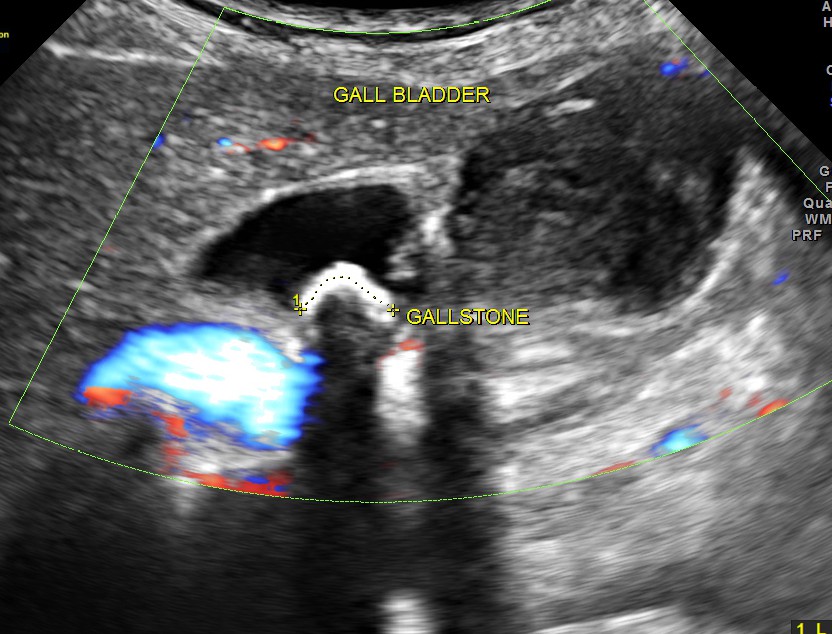

Ultrasound showed the following – Gallstone with irregular growth in the fundus of the gall bladder , above the phrygian cap.

The fundus shows irregular growth and a gallstone.